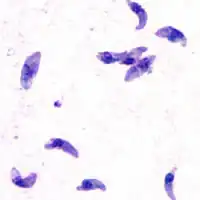

Giemsa stained T. gondii tachyzoites, 1000× magnification

Tachyzoites

Motile, and quickly multiplying, tachyzoites are responsible for expanding the population of the parasite in the host.[47][30]: 19  When a host consumes a tissue cyst (containing bradyzoites) or an oocyst (containing sporozoites), the bradyzoites or sporozoites stage-convert into tachyzoites upon infecting the intestinal epithelium of the host.[30]: 359  During the initial acute period of infection, tachyzoites spread throughout the body via the blood stream.[30]: 39–40  During the later, latent (chronic) stages of infection, tachyzoites stage-convert to bradyzoites to form tissue cysts. To survive in the host, tachyzoites manipulate the immune response by injecting the contents of rhoptries into host cells. This seems to be vital for their survival, as knock-out strains of T. gondii which are unable to inject hosts with rhoptries have been shown to be avirulent in vivo.[29]